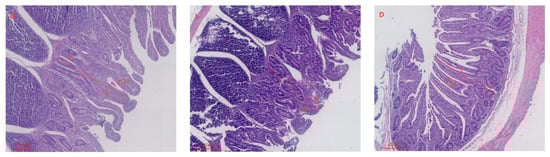

Effects of Supplementation with Dimethylglycine Sodium Salt on Immunity, Intestinal Tissue Morphology, and Antioxidant Function in IUGR Lambs

by Yuwei Wang, Mengfei Li, Lin Ma, Yurong Lin, Cheng Zhang, Zhiqiang Cheng, Yong Chen and Changjiang Zang

Animals 2026, 16(8), 1258; https://doi.org/10.3390/ani16081258 - 20 Apr 2026

This study investigates the regulatory effects of dietary supplementation with DMG-Na on growth performance, immunity, and intestinal development in IUGR lambs. A total of 45 lambs were used: thirty IUGR (3.10 ± 0.16 kg) lambs were randomly assigned to IUGR or IUGR + [...] Read more.

This study investigates the regulatory effects of dietary supplementation with DMG-Na on growth performance, immunity, and intestinal development in IUGR lambs. A total of 45 lambs were used: thirty IUGR (3.10 ± 0.16 kg) lambs were randomly assigned to IUGR or IUGR + DMG-Na (0.1% in milk replacer from days 7–56) groups, with fifteen normal birth weight lambs as CON (4.32 ± 0.17 kg). At 56 days of age, eight lambs per group were slaughtered for sample collection. Compared to CON, IUGR lambs showed a significantly lower final body weight and average daily gain (ADG) (p < 0.01); IUGR also severely compromised intestinal structure, markedly decreasing villus height and villus height-to-crypt depth ratio across all small intestinal segments (p < 0.01); immune function was impaired, with highly significantly lower jejunal secretory IgA (sIgA) (p < 0.01); and antioxidant capacity was diminished, evidenced by reduced jejunal GSH, catalase (CAT) and glutathione reductase (GR) activities (p < 0.05) and increased jejunal MDA content (p < 0.01). Compared to IUGR, IUGR + DMG-Na group had highly significant increased final body weight and significant increased ADG (p < 0.01); it enhanced intestinal morphology, notably increasing villus height and villus height-to-crypt depth ratio in the duodenum and jejunum (p < 0.01); immune markers improved, with elevated jejunal sIgA (p < 0.05); and antioxidant status was restored, demonstrated by increased jejunal GSH and CAT activities (p < 0.05) and decreased jejunal MDA content (p < 0.01). In conclusion, DMG-Na effectively counteracted IUGR-induced deficits by promoting intestinal development, immunity, and antioxidant capacity, ultimately improving growth performance. Full article